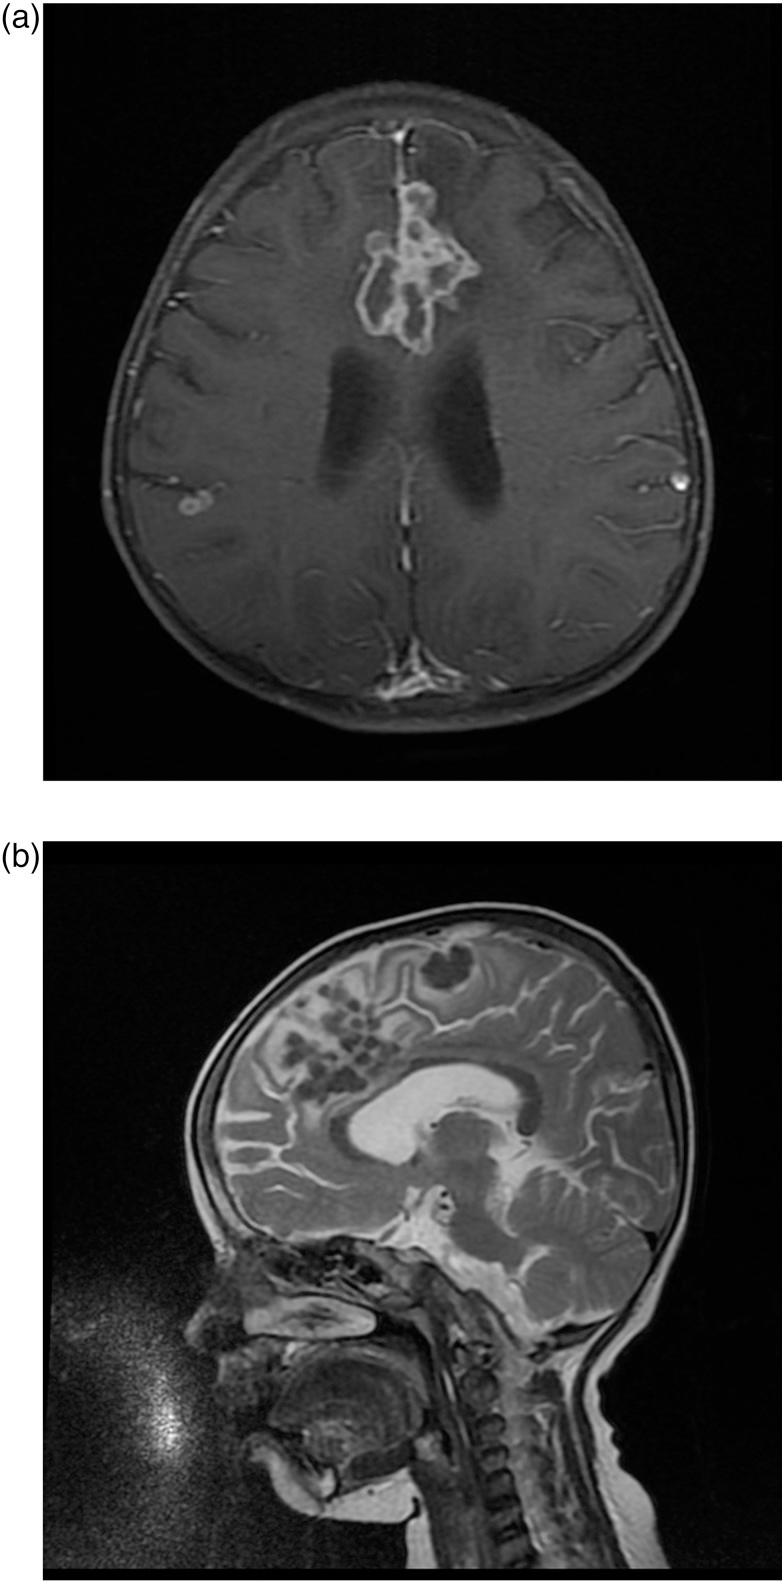

Tuberculomas are usually infratentorial in children, and supratentorial lesions predominate in adults. We present a 4-year-old girl with multiple seizures, papilloedema and brisk reflexes. On investigation, she was found to have a large left parafalcine tuberculoma. She was treated with antitubercular treatment (ATT) and steroids. The child improved, seizures stopped and the papilloedema gradually disappeared. Follow-up magnetic resonance imaging brain after 8 months showed a mild reduction in the size of the lesion. Child is on regular follow-up.